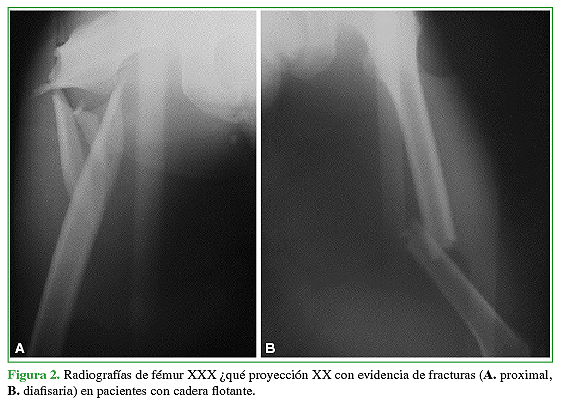

El término “flotante” relacionado con alguna articulación indica una disrupción esquelética por encima y por debajo de ella, que puede ser intrarticular o extrarticular. Este término fue introducido por Blake y McBryde, en 1975, para describir la rodilla flotante.1 En nuestro caso, nos referimos a una situación poco común en la que están involucradas una fractura de fémur con una fractura de pelvis o de acetábulo homolateral y que requerirán un tratamiento quirúrgico específico en forma secuencial (Figuras 1y 2).2

Con respecto a los pacientes del grupo 1 (CF), el 60,9 % (n = 14) eran hombres y el 39,1%, mujeres (n = 9), con un promedio de edad de 30 años (DE = 10). El mecanismo de lesión fue la colisión de motocicleta contra automóvil (78,2%, n = 18), automóvil contra automóvil (13%, n = 3) y caída de propia altura (8,8%, n = 2). El 60,8% de los pacientes (n = 14), tenía una clasificación tipo A de Liebergall; el 30,45% (n = 7), tipo B y el 8,7% (n = 2) tipo C. El tiempo promedio de seguimiento fue de 4.6 años (rango 1.2-5).

La fractura de fémur había sido tratada con clavos endomedulares en el 95,7% (n = 22) (Figura 6) y con placa y tornillos solo en el 4,3% (n = 1). La mediana de días de internación de esta población fue de 8 (rango 5-10). La mediana de la duración de los procedimientos fue de 247 min (rango 120-480) y la mediana de la pérdida hemática estimada durante la operación, de 500 ml (rango 300- 900).